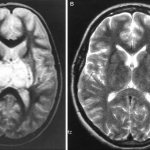

Hypoxic syndrome develops very quickly with the formation of hypoxic coma. A general clinical and physical examination may be sufficient for diagnosis. To clarify, two methods are used: radiography and ECG. The radiograph shows intense homogeneous darkening of the lung tissue in the central part and roots in the form of “butterfly wings”, or infiltrative-like darkening in the form of a “snow blizzard”. With pulmonary embolism, the darkening has a triangular shadow directed at an acute angle towards the root of the lung. With bronchial occlusion, pulmonary atelectasis is formed with homogeneous darkening of the lung tissue with a shift of the mediastinum towards the darkening, especially if the picture is taken during inspiration.

Physical examination reveals dullness of percussion sound, lag of the affected side in the respiratory act, hard breathing, in some cases with a bronchial tinge. There are wheezing (dry or wet). X-ray can detect inflammatory infiltration of lung tissue without clear boundaries. A tomography method is relevant, which detects the presence of vacuum in the infiltration zone in case of lung abscess.

An x-ray reveals an oval or round cavity containing fluid or air; a zone of perifocal inflammation is recorded, which decreases with treatment. If the course is favorable, the abscess will scar within 3-4 weeks. If it exists for more than 3 months, doctors talk about a chronic abscess, which can only be cured with surgery.

It is recorded mainly in children, not adults. The course is rapid, hypoxia and intoxication syndrome appear. Hypoxic eclampsia often occurs. When coughing (persistent), an increasing amount of purulent sputum occurs. Auscultation reveals weakened breathing and cacophonous wheezing. X-ray shows extensive infiltration of lung tissue. On the second or third day after the onset of the disease, multiple cavities located in the cortical layer of the lung are recorded. The process very soon affects the pleura, pleurisy is formed. On the third day, the pleura generally breaks through, resulting in the formation of pyopneumothorax.

An X-ray of pulmonary gangrene shows darkening of the lung tissue. By the third, fourth or fifth day, several or one cavity is formed. The course in many cases becomes complicated over time by pulmonary hemorrhages, purulent pleurisy or sepsis.